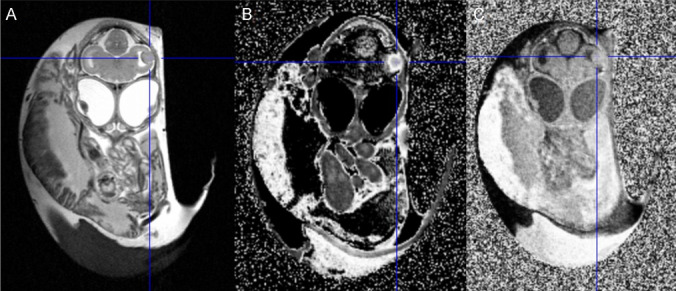

Procedures: Human U87 glioblastoma cells and U87-IDH1 mutant glioma cells were implanted into the brains of chick embryos at developmental day 5. After 12-14 days of tumour growth, blood-brain-barrier integrity was evaluated in vivo using MRI contrast enhancement or ex vivo with Evans blue dye. The tracers O-(2-[18F]fluoroethyl)-L-tyrosine ([18F]FET) (n = 5), 3,4-dihydroxy-6-[18F]-fluoro-L-phenylalanine ([18F]FDOPA) (n = 3), or [68Ga] labelled quinoline-based small molecule fibroblast activation protein inhibitor ([68Ga]FAPI-46) (n = 4) were injected intravenously if solid tumours were detected with MRI. For time-activity curves for [18F]FET, additional micro PET (µPET) was performed. The chick embryos were sacrificed 60 min post-injection, and cryosections of the tumour-bearing brains were produced and evaluated with autoradiography and immunohistochemistry.

Results: Intracerebral tumours were produced with a 100% success rate in viable chick embryos at the experimental endpoint. However, 52% of chick embryos (n = 85) did not survive the procedure to embryonic development day 20. For the evaluated radiotracers, the tumour-to-brain ratios (TBR) derived from ex vivo autoradiography, as well as the tracer kinetics derived from µPET for intracerebral chick embryo tumours, were comparable to those previously reported in rodents and patients: the TBRmean for [18F]FET was 1.69 ± 0.54 (n = 5), and 3.8 for one hypermetabolic tumour and < 2.0 for two isometabolic tumors using [18F]FDOPA, with a TBRmean of 1.92 ± 1,11 (n = 3). The TBRmean of [68Ga]FAPI-46 for intracerebral chick embryo tumours was 19.13 ± 0.64 (n = 4). An intact blood-tumour barrier was observed in one U87-MG tumour (n = 5).